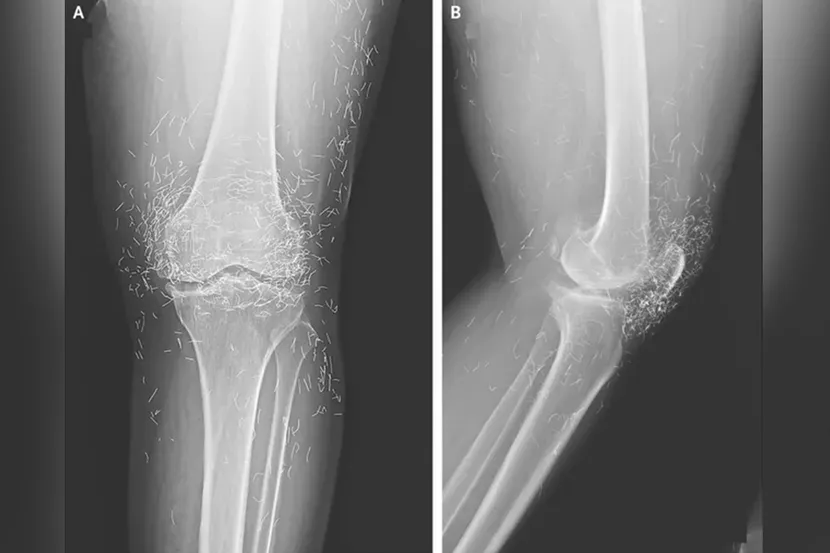

Imagine going to the doctor for creaky knees and finding out you’re basically a walking treasure chest! A 65-year-old woman in South Korea stunned her doctors when they discovered hundreds of gold threads woven into her knees from a questionable acupuncture adventure. Instead of relief, she got a glittering surprise and a warning: this “golden” treatment might make your MRI scans as risky as a pirate’s treasure hunt!

Doctors Find Threads of Pure Gold in Woman’s Knees